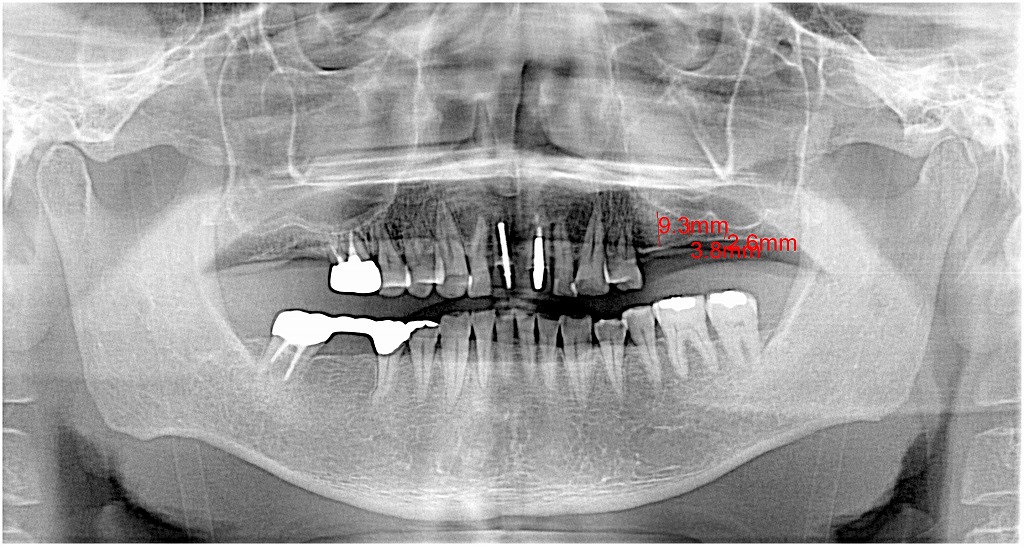

術前のパノラマになります

左側の左下の5,6,7番部が大きく転出してきていました

左上のインプラントは骨幅がなく3mm、4mmという世界です